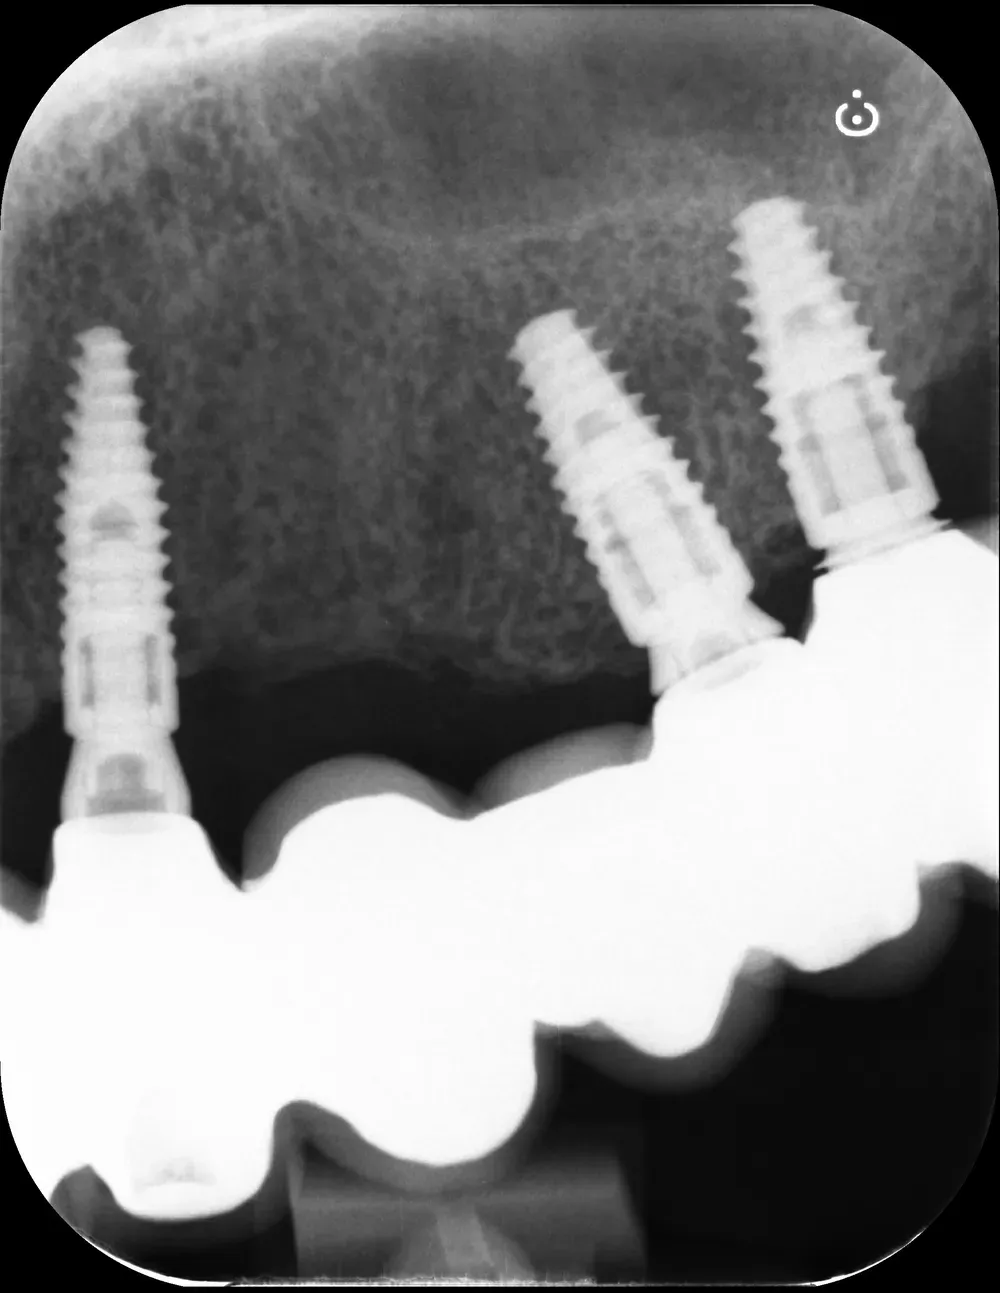

Le immagini sottostanti illustrano la situazione ossea pre-operatoria della cresta alveolare, con una grave atrofia orizzontale, corrispondente alla categoria H3 della Classificazione di Colonia (CCARD).

Secondo la BDIZ EDI, tale grado di atrofia controindica le tecniche espansive.

Personalmente, tuttavia, ritengo che con gli strumenti moderni sia possibile e consigliabile spingersi oltre per includere anche tale livello di atrofia tra le indicazioni. E questo caso lo dimostra.

Il mascellare superiore destro era affetto da atrofia categoria S3 CCARD in posizione 16 e S2 CCARD in posizione 14 (precedentemente estratto), con presenza di cisti da ritenzione mucosa e setto di Underwood.

Inserimento impianti con rialzo del seno e aspirazione cisti da ritenzione mucosa del seno mascellare

Ho inserito due impianti, in posizione appunto 16 e 14, con minirialzo del seno mascellare e aspirazione della cisti da ritenzione mucosa tramite accesso laterale.